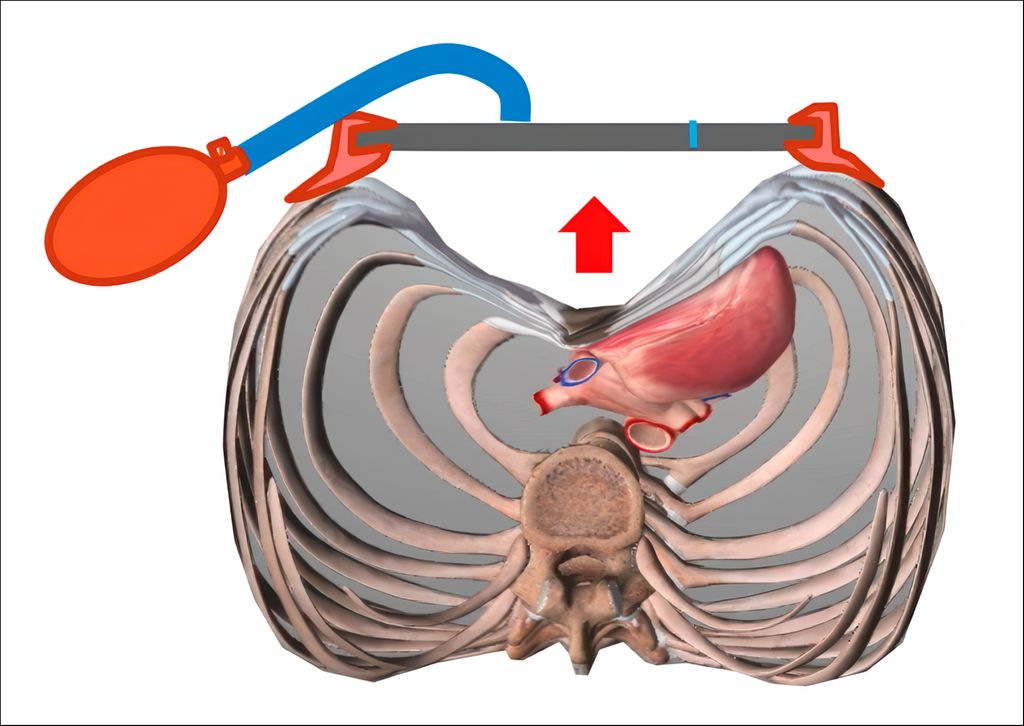

In mittel- bis höhergradigen Fällen kommt es im Zuge des zunehmenden Mediastinalshifts zu einer Linksverlagerung sowie auch einer Kompression des Herzens, wo mechanisch vor allem das rechte Kammersystem betroffen ist.6,7Der rechte Ventrikel ist eingeengt, verliert an Compliance und nimmt in der radiologischen Darstellung eine „tubuläre Form“ an. Damit sinkt auch die „ejection fraction“ und damit insgesamt der „cardiac output“ (Abb.2). Eine Situation, die therapeutisch nachweislich verbessert werden kann.8

Bei Erwachsenen und bei steiferem Thorax muss, so wie auch bei deutlichen Verwachsungen im vorderen Mediastinum, die herkömmliche einfache minimalinvasive Trichterbrustkorrektur durch zusätzliche operative Maßnahmen, additiv zu den eingepflanzten Implantaten, erweitert werden.1,18 Sie beinhalten die thorakoskopische partielle Schlitzung des Perichondriums betroffener Rippen, die gerade oder schräge partielle Sternumosteotomie (z.B. zum Ausgleich der Krümmung bzw. der Rotation), ggf. Rippenknorpelresektionen (Stichwort: vorgewölbte Rippenbögen) und ggf. eine anterior-mediastinale Dissektion (Mediastinotomie) im vorderen Mediastinum zwischen Sternum und Herzbeutel (Abb.7a+b). Letztere Maßnahme erfordert einen zusätzlichen medianen subxiphoidalen Zugang zum Mediastinum.